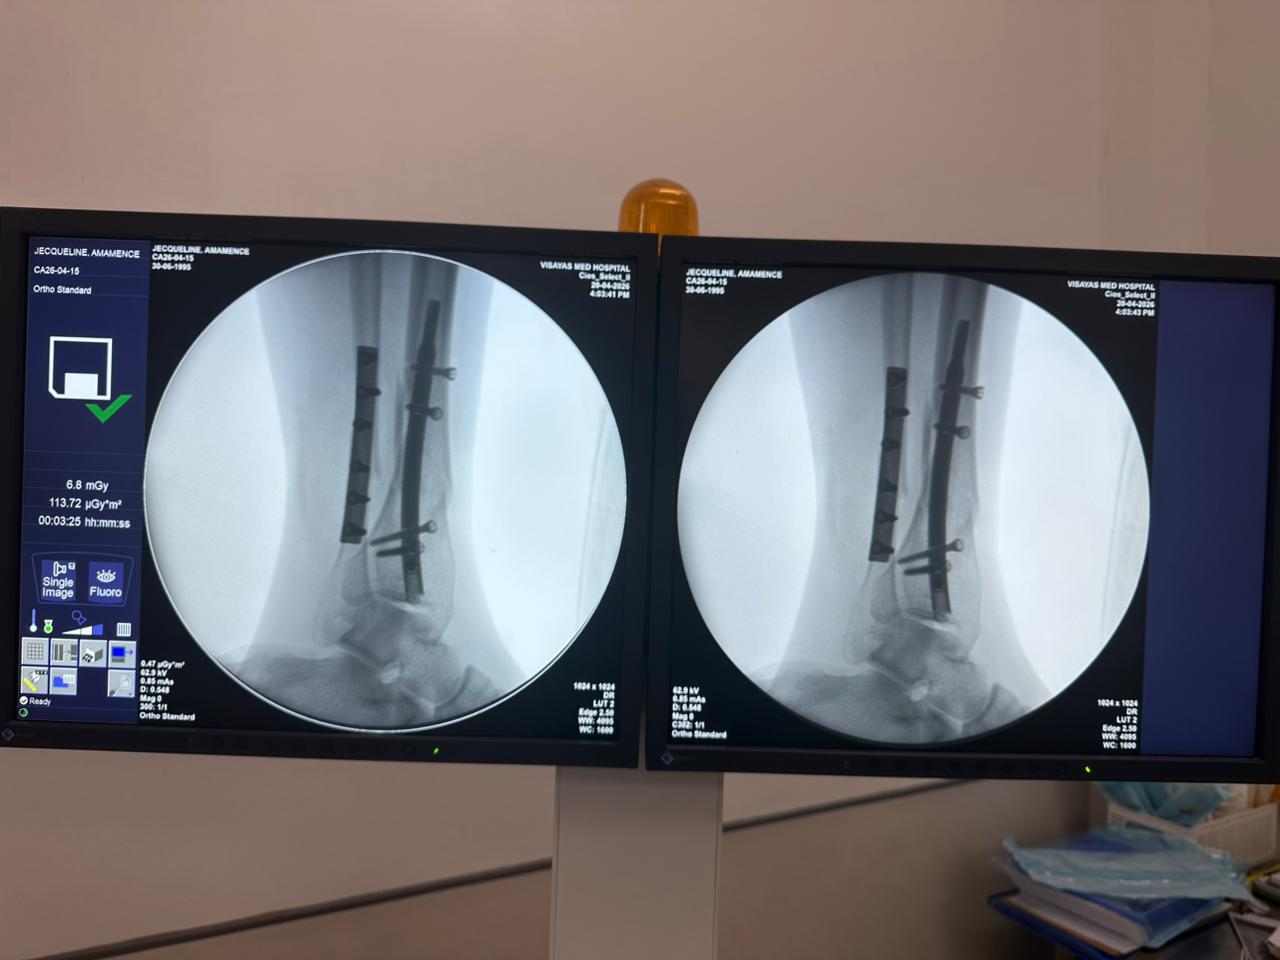

Distal Tibial Nail Fixation Case Study with Fibular Plate Support

Patient:

31-year-old patient

Surgical Area:

Distal tibia and fibula

Product Used:

Distal Tibial Nail

Fibular Locking Plate

Imaging:

Intraoperative C-arm fluoroscopy, AP and lateral views

Case Summary:

This case involved distal tibial fixation using an intramedullary distal tibial nail. Intraoperative fluoroscopy confirmed the position of the nail, distal locking screws, and fibular plate fixatio